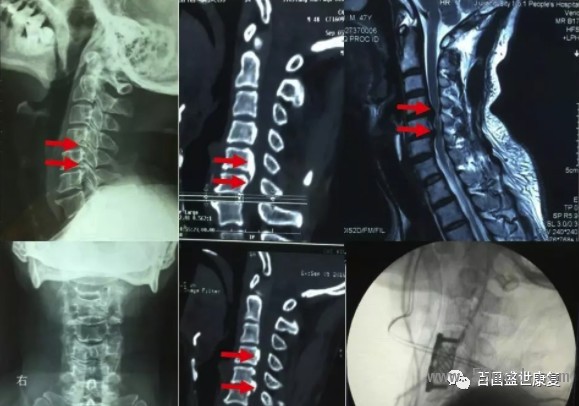

由于該型頸椎病起病隱匿,發(fā)作很緩慢,因此很多患者得不到及早診斷,就診時(shí)候已經(jīng)出現(xiàn)脊髓信號(hào)改變,從而導(dǎo)致不可逆性脊髓損傷。

因此對(duì)于此類(lèi)型頸椎病患者,但凡有癥狀懷疑此型頸椎病時(shí),早期頸椎核磁共振檢查十分必要,若核磁共振提示脊髓壓迫導(dǎo)致脊髓信號(hào)改變,應(yīng)該盡快實(shí)施手術(shù)。

不同類(lèi)型頸椎病表現(xiàn)不一樣,也有部分患者為混合上述分型中的一種或者多種類(lèi)型,也叫混合型頸椎病。不同患者對(duì)疾病耐受程度不一樣,有些患者癥狀很?chē)?yán)重,影像學(xué)檢查卻很輕;部分患者癥狀很輕微,影像學(xué)檢查已經(jīng)出現(xiàn)很?chē)?yán)重的退變和脊髓神經(jīng)壓迫表現(xiàn)。

因此既不能單純根據(jù)癥狀判斷疾病的嚴(yán)重程度,也不能單純根據(jù)影像學(xué)病變確定治療方案。典型的臨床表現(xiàn),結(jié)合科學(xué)的影像學(xué)檢查綜合判斷,有助于確定頸椎病類(lèi)型和疾病的嚴(yán)重程度,從而選擇合適治療方案。